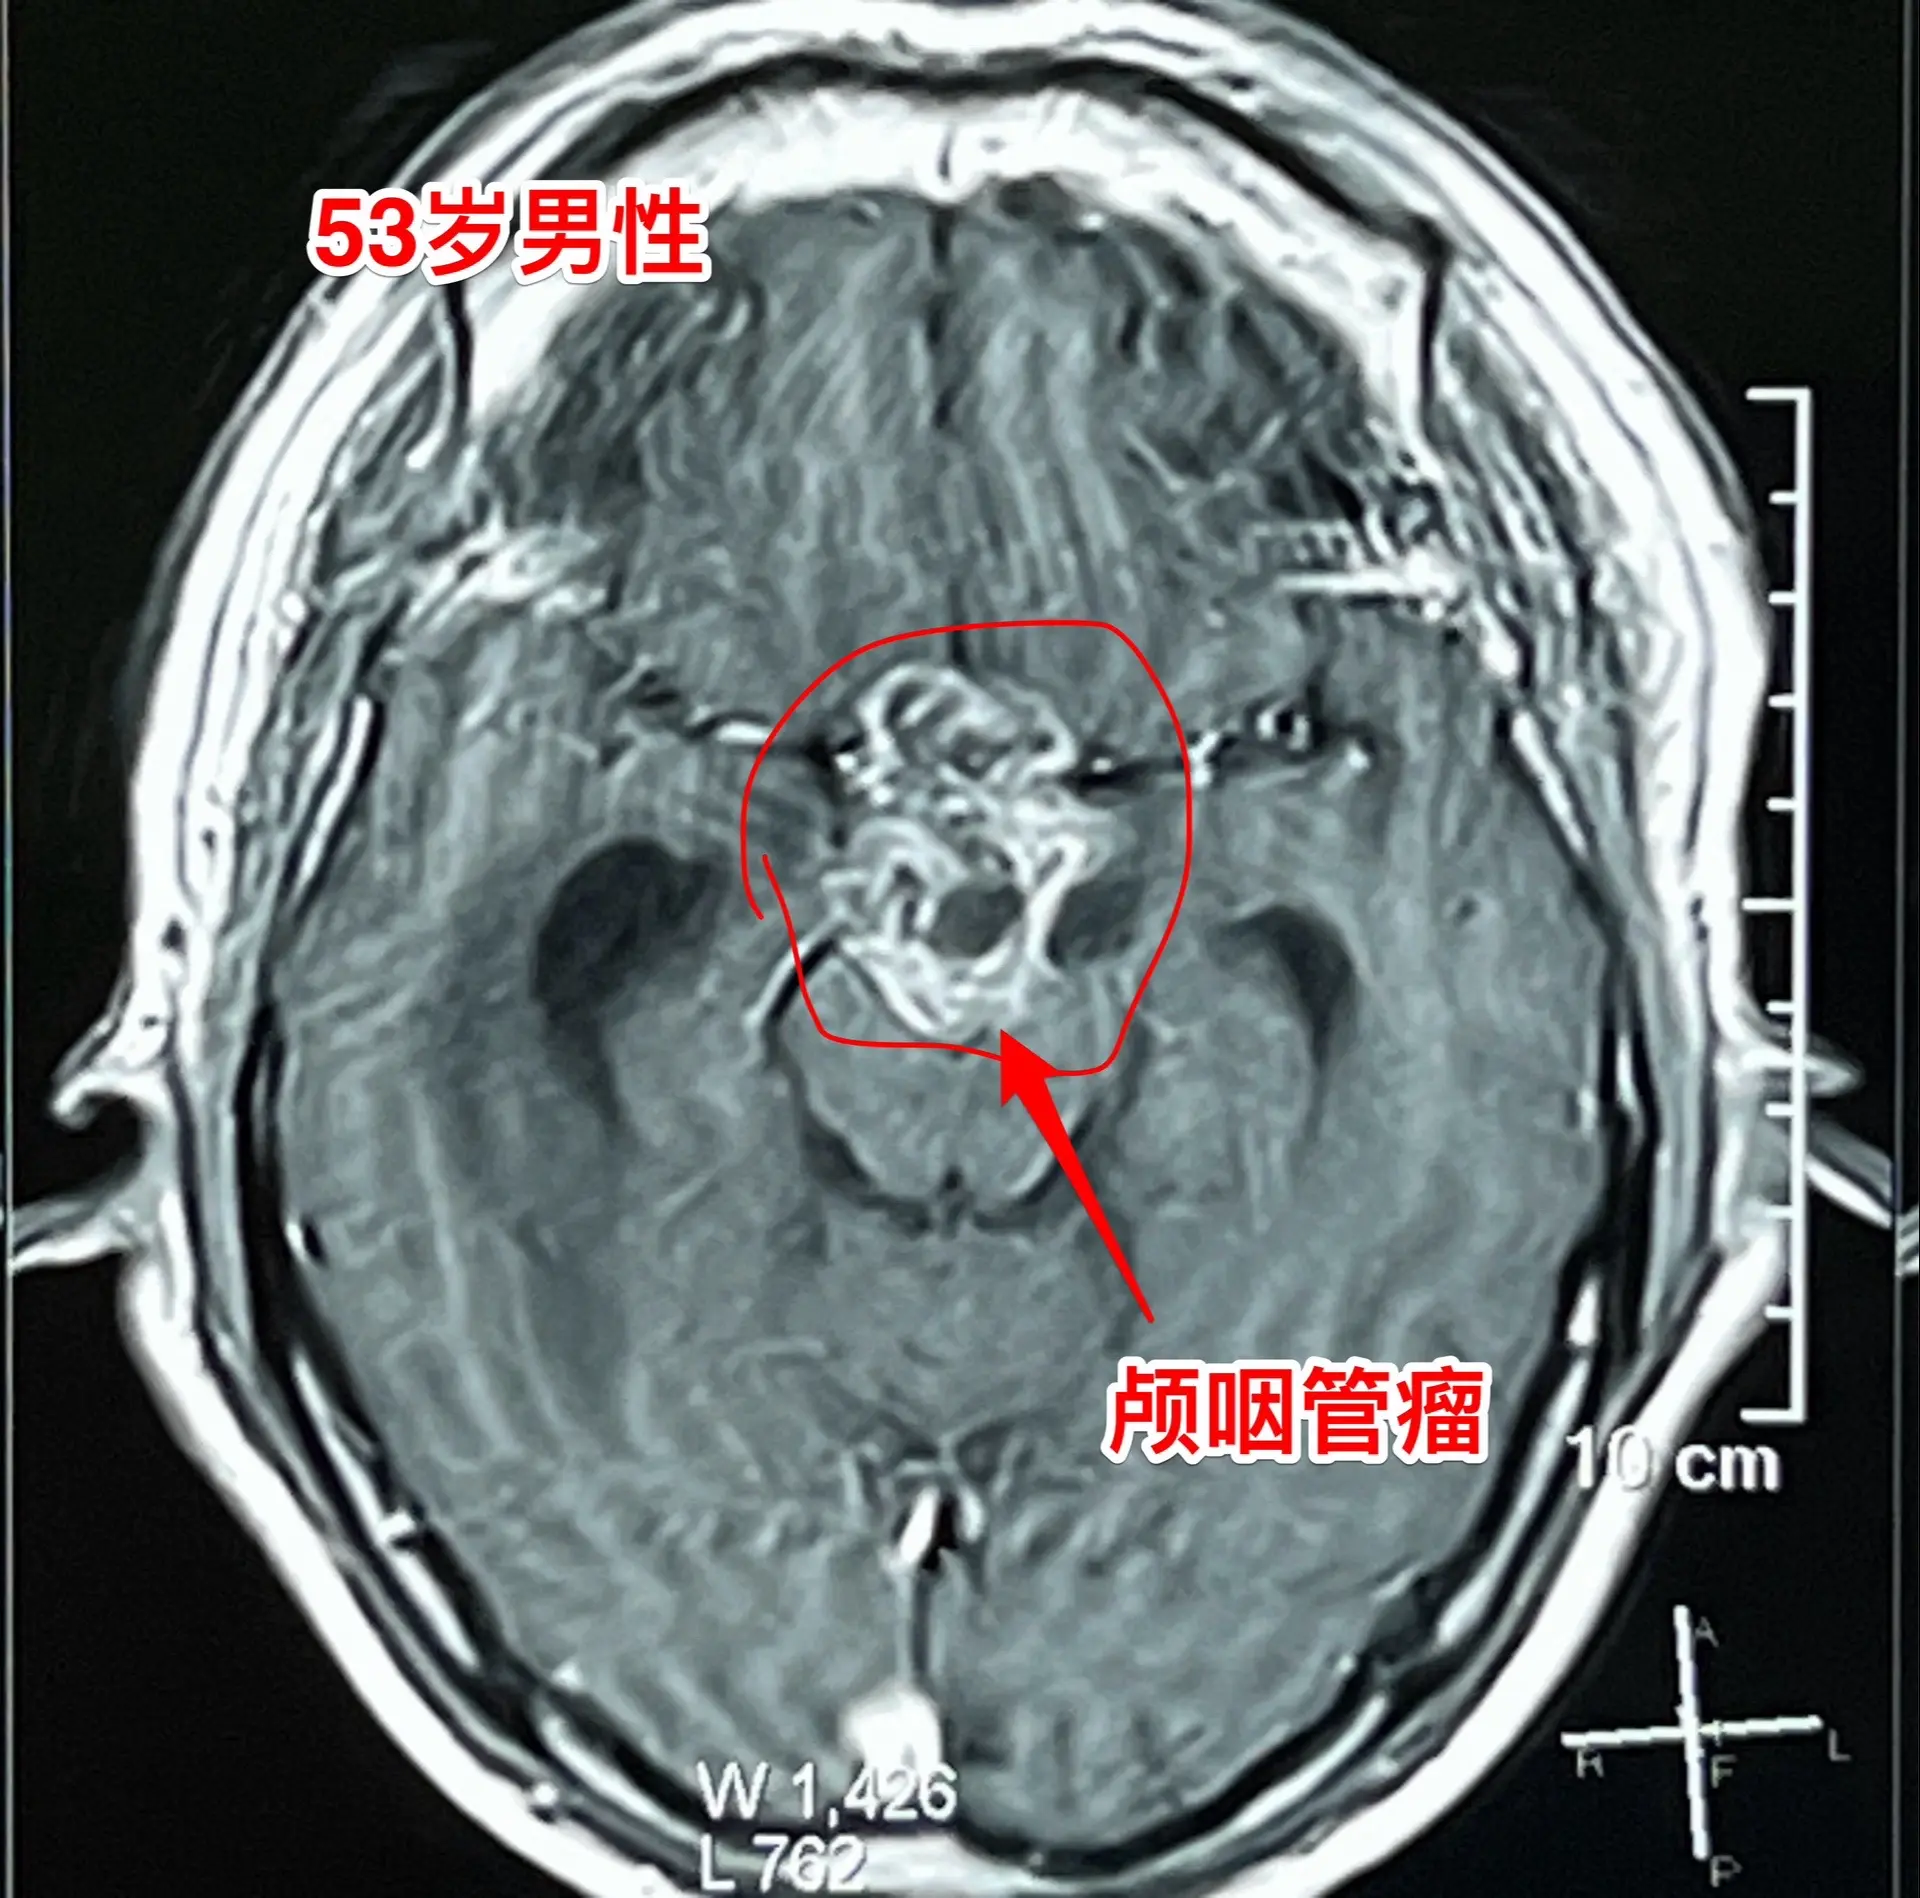

到医院作脑部磁共振检查,发现了脑部长了一个大肿瘤-颅咽管瘤,伴有脑积水。这个肿瘤直径接近5厘米,几乎是实性肿瘤,有很多的钙化斑,见图

思维糊涂、行走不稳、尿失禁这三个症状都是脑积水造成的。

而脑积水是颅咽管瘤堵塞脑室系统造成的。